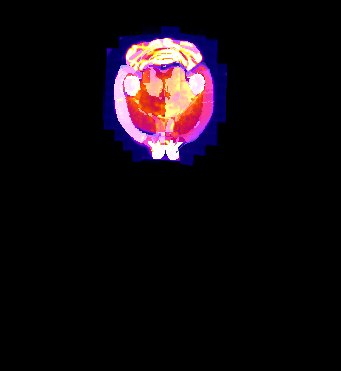

| Overlay of co-aligned CT scan and brain atlas-staining | Overlay of co-aligned CT scan and DAPI-staining | Overlay of co-aligned brain Atlas and DAPI-staining |